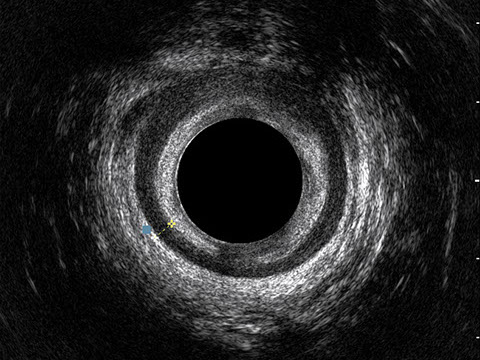

L’ecografia transanale è un esame diagnostico per immagini che consiste nell’introduzione di un trasduttore ad ultrasuoni. Le immagini qualitativamente migliori del canale anale sono ottenute usando un trasduttore rotante, montato in un manipolo rigido, che fornisce un’immagine a 360°. Con le apparecchiature più moderne è anche possibile ottenere immagini tridimensionali.

L’ecografia transanale permette di distinguere la sottomucosa che riveste il canale anale, lo sfintere anale interno, e lo sfintere anale esterno.

Proctal dispone di apparecchiatura per ecografia endoanale 3D con sonda rotante.